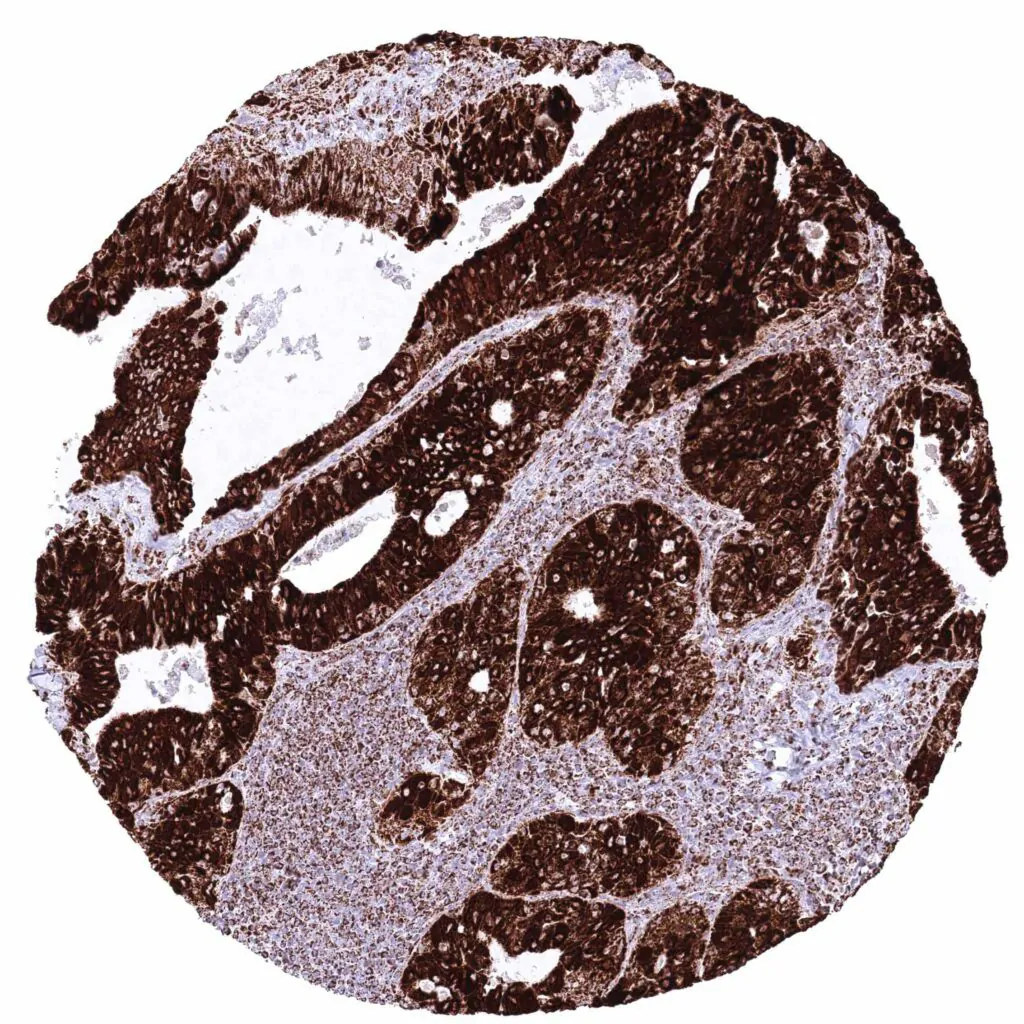

Colon – Colorectal adenocarcinoma with strong cytoplasmic ATP5J staining of all tumor cells.